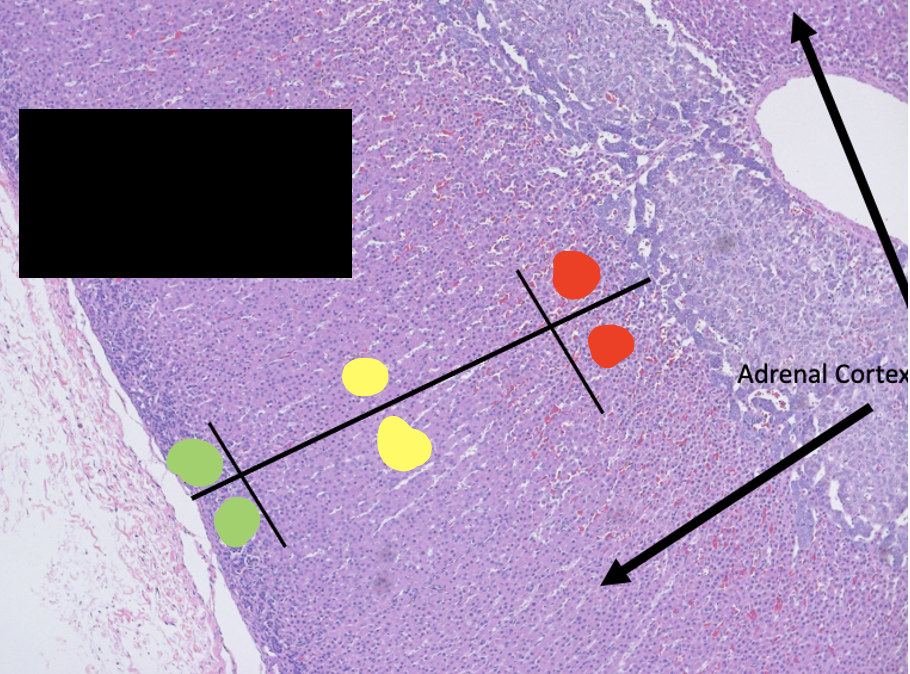

adrenal gland

Red –> cortex

Black –> medulla

Green –> zona glomerulosa

Yellow –> zona fasciculata

Red–> zona reticularis